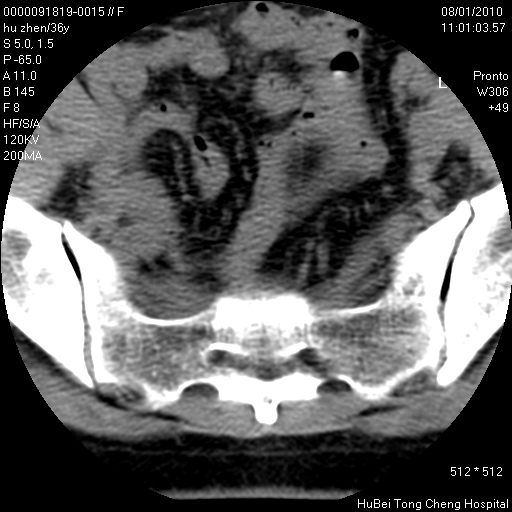

患者 女,36岁。右侧腰腿痛半月余。腰骶椎mr平扫偶然发现骶椎异常信号。

临床诊断:1)腰椎间盘突出症。2)骶椎肿瘤性病变?

骶椎ct平扫(层厚、层距均为5mm),图像如下: